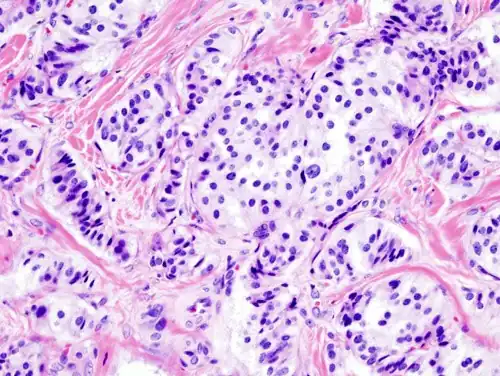

| Pathology of pancreatic endocrine tumour (insulinoma). | |